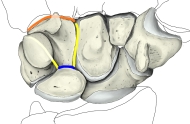

・「日本人体解剖学 (上巻) 「楔状で、近位側、遠位側および外側には関節面を有し、掌側面には先端のやや外側に曲がった突起がある。これを有鈎骨鈎という。 」 また、「船戸和弥のホームページ」では以下のようになっている。 「有鈎骨は第4、5中手骨に対する不正な鞍状の関節面を底として上方に尖る三角形である。掌側面の内側端から掌側に有鈎骨鈎が突出する。内上面は三個角骨にする鞍状の関節面で占められる。」 そして、以下は「Wikipedia」からの抜粋文となる。 The hamate bone has six surfaces:

・イラストや写真を掲載しているサイトⅠ(左手・手背面のCG) ・イラストや写真を掲載しているサイトⅡ(2方向からの単体のイラスト) ・イラストや写真を掲載しているサイトⅢ(筋の付着が分かるイラスト) ・イラストや写真を掲載しているサイトⅣ(手根骨周辺の断面、赤は有頭骨) ・イラストや写真を掲載しているサイトⅤ(レントゲン画像、手根骨周辺) ・イラストや写真を掲載しているサイトⅥ(レントゲン画像、前腕下部~中手骨)

有鈎骨は以下の7つの骨と接し、3種類の関節を作っている。